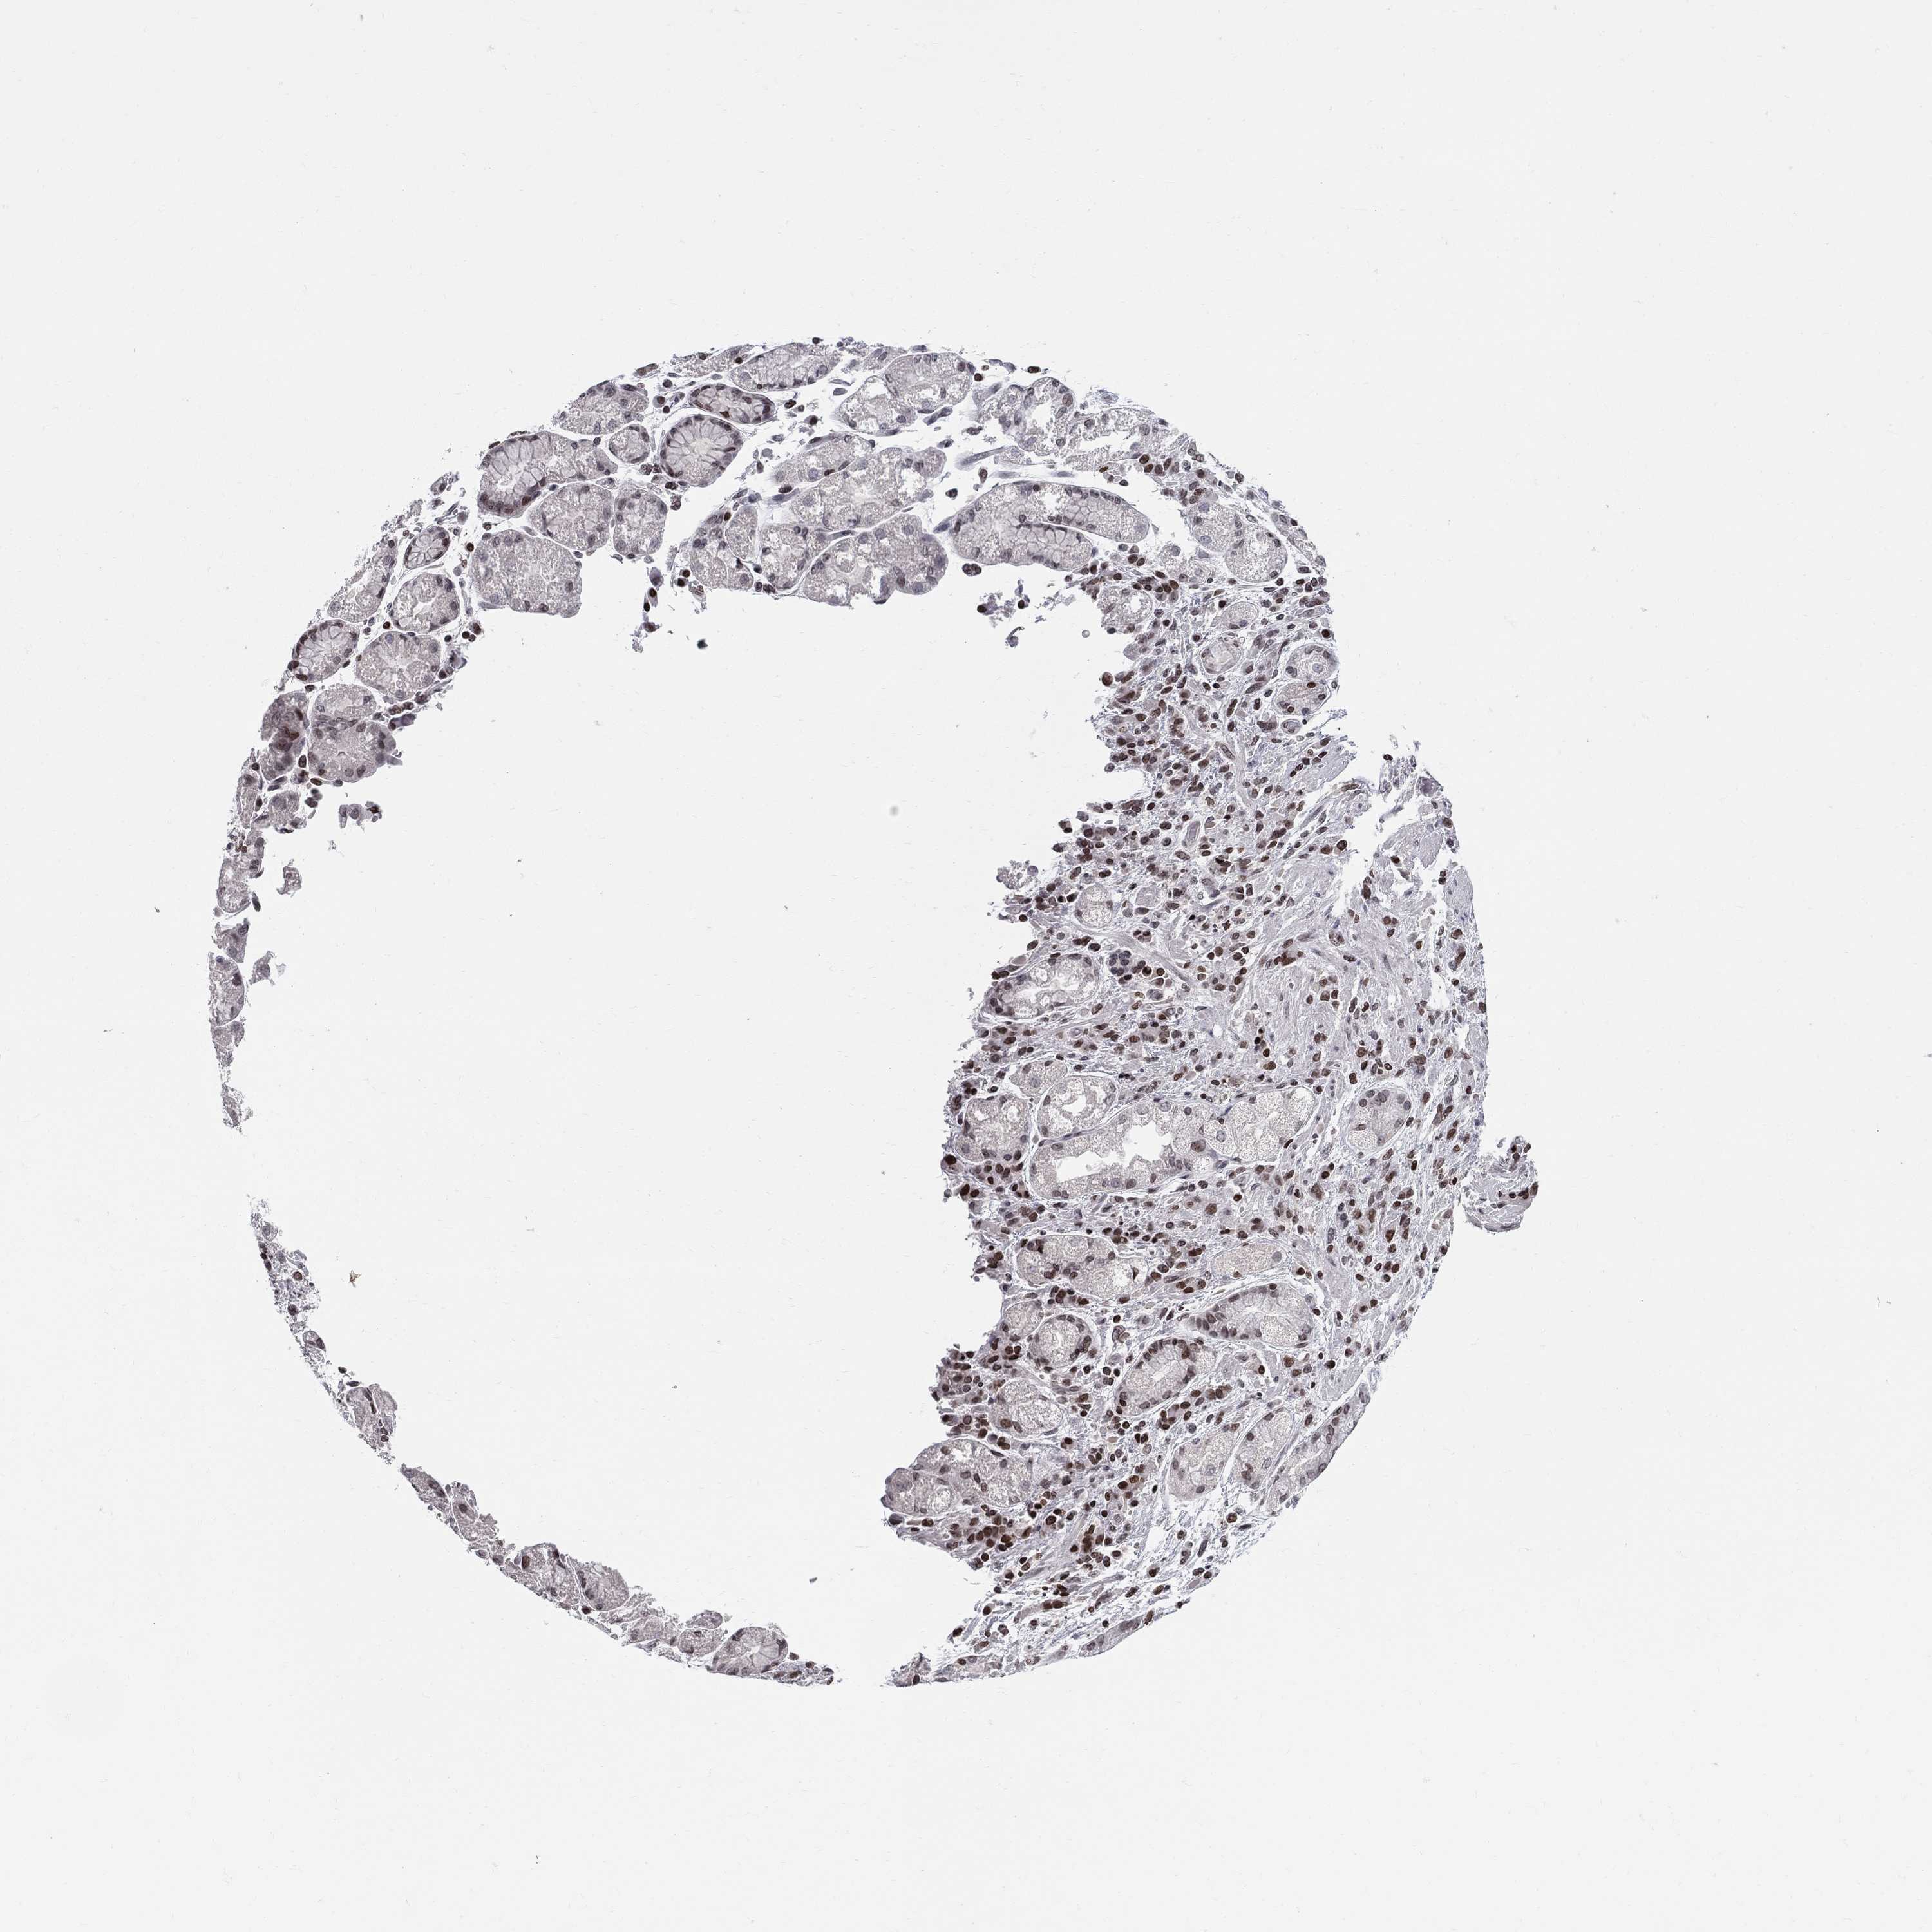

STOMACH CANCER - Protein expressioni

A mouse-over function shows sample information and annotation data. Click on an image to view it in a full screen mode. Samples can be filtered based on level of antibody staining by selecting one or several of the following categories: high, medium, low and not detected. The assay and annotation is described here.

Note that samples used for immunohistochemistry by the Human Protein Atlas do not correspond to samples in the TCGA dataset.

Antibody stainingi

Antibody staining in the annotated cell types in the current human tissue is reported as not detected, low, medium, or high, based on conventional immunohistochemistry profiling in selected tissues. This score is based on the combination of the staining intensity and fraction of stained cells.

Each image is clickable and will lead to virtual microscopy that enables deeper exploration of all samples and also displays staining intensity scores, fraction scores and subcellular localization as well as patient and tissue information for each sample.

Antibody HPA065375

Staining

High

Medium

Low

Not detected

Intensity

Strong

Moderate

Weak

Negative

Quantity

>75%

75%-25%

<25%

None

Location

Nuclear

Cytoplasmic/membranous

Cytoplasmic/membranous,nuclear

Adenocarcinoma, NOS